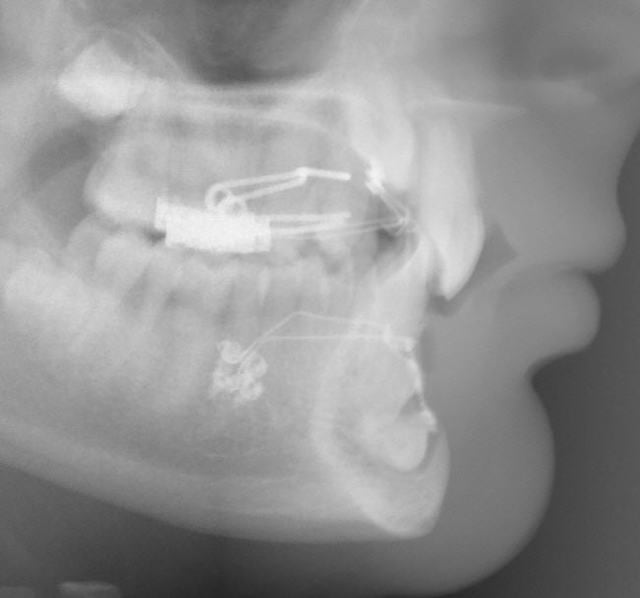

En pièces jointes, les radios de contrôle faites à 11h45. Je n’ai pas encore eu le temps de traiter les photos.

4 canines otp da6shp - Eugenol

4 canines tele pjw3hq - Eugenol